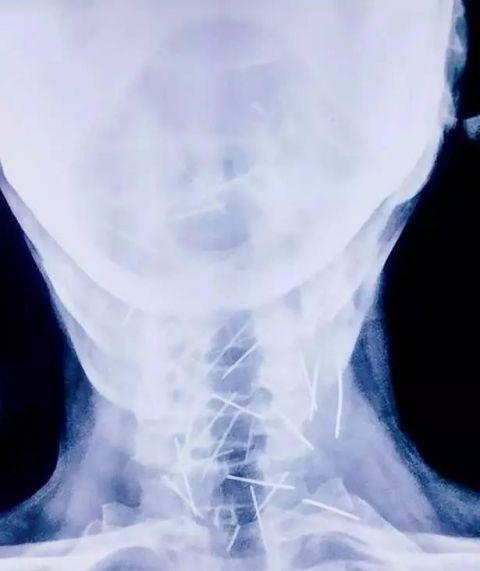

男子的全身都插满了钢针,后来仔细确认总共有75根钢针,其中40根在喉咙上,还有25根在右腿,其余的钢针在手臂上。

不过幸运的是钢针没插在内脏上,因此男子暂时保住自己一命,但是当地的医院都拒绝为他取钢针,男子只好等待找到合适的意愿,躺在病床上。